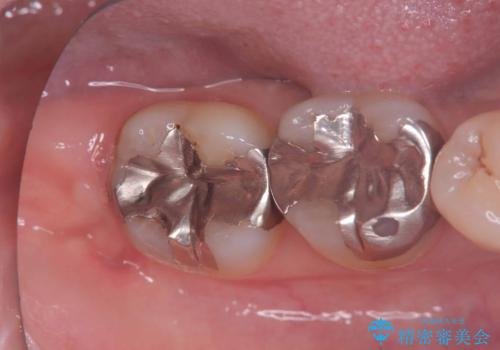

根管治療を行ったのち、症状改善を認めオールセラミッククラウンにて修復治療を行いました。

根管治療を行った歯は、再発防止や残された歯質を守るため、クラウンによる補綴治療が必要となります。